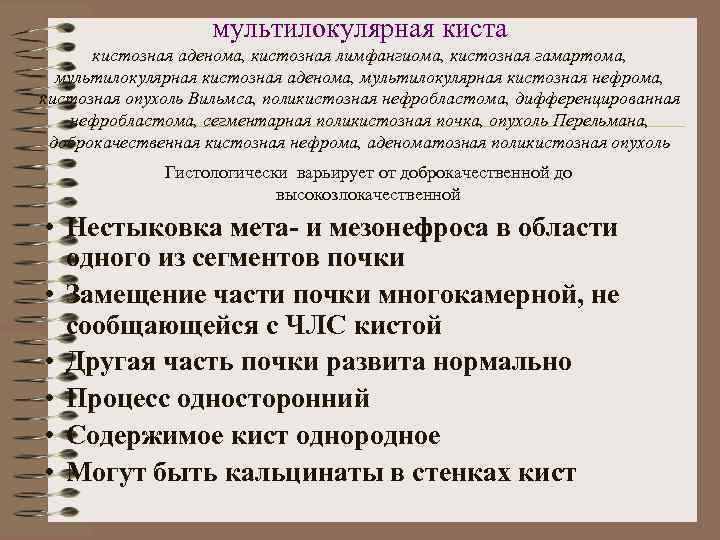

мультилокулярная киста кистозная аденома, кистозная лимфангиома, кистозная гамартома, мультилокулярная кистозная аденома, мультилокулярная кистозная нефрома, кистозная опухоль Вильмса, поликистозная нефробластома, дифференцированная нефробластома, сегментарная поликистозная почка, опухоль Перельмана, доброкачественная кистозная нефрома, аденоматозная поликистозная опухоль Гистологически варьирует от доброкачественной до высокозлокачественной • Нестыковка мета- и мезонефроса в области одного из сегментов почки • Замещение части почки многокамерной, не сообщающейся с ЧЛС кистой • Другая часть почки развита нормально • Процесс односторонний • Содержимое кист однородное • Могут быть кальцинаты в стенках кист